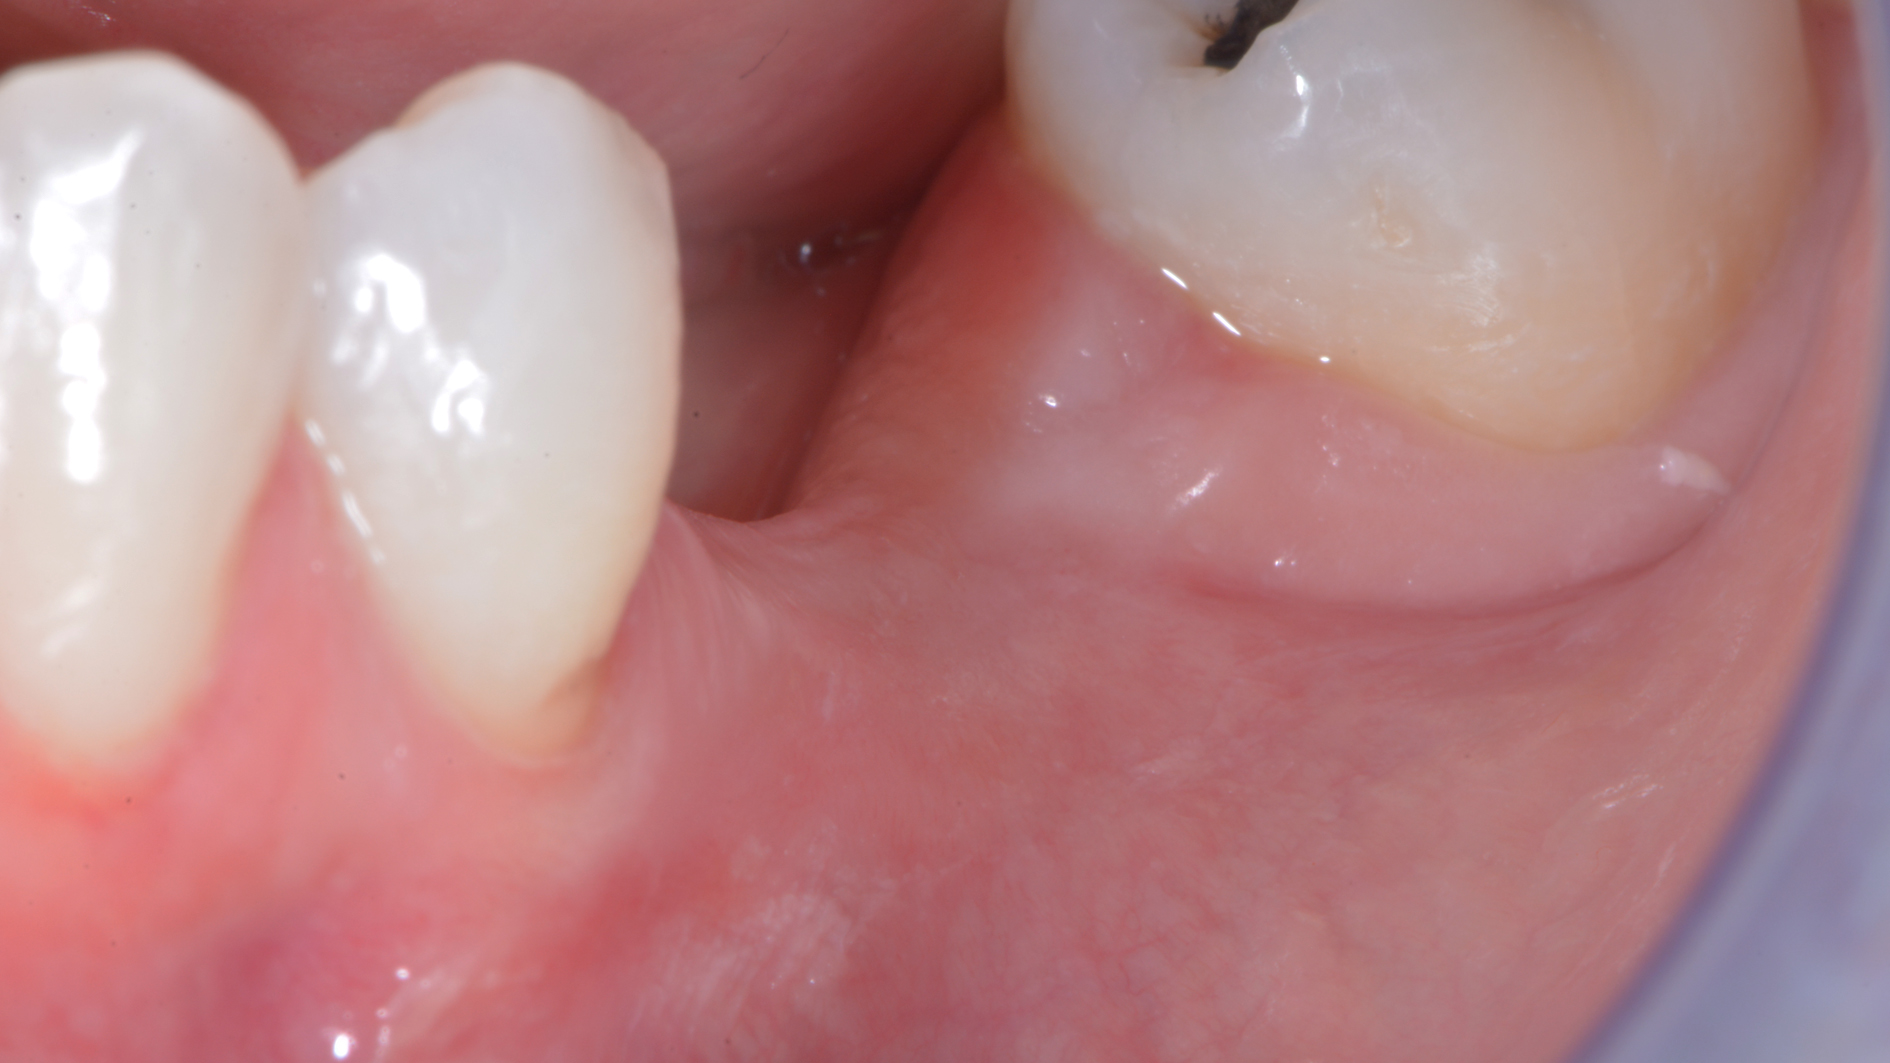

Come credi che si possa risolvere un caso come questo…

DSC_6241

o come questo…

Sconosciuto-X-20151123-200312-XYHMH6ZQBS2X-4

senza tecniche di chirurgia avanzata?

Attenzione a non confondere: ho detto avanzata. Non invasiva.